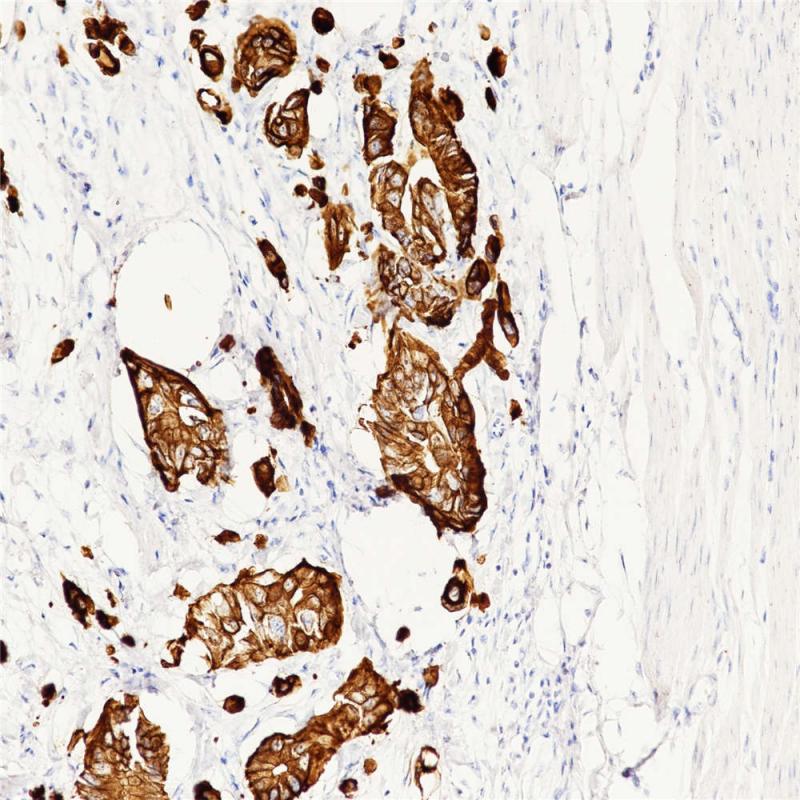

CK20是一种具有限制表达模式的单层上皮角蛋白,其II型配对通常为CK8。CK20在正常组织表达于胃小凹上皮、大小结肠上皮、膀胱上皮、一些神经内分泌细胞以及Merkel细胞。肿瘤组织中,CK20表达于结肠腺癌,胃腺癌,胰腺癌,胆管癌,卵巢粘液腺癌,尿路上皮癌以及Merkel细胞癌。CK20通常与CK7及其他抗体联合表达,用于区分结肠癌(CK20+)和卵巢癌,肺癌及乳腺癌。

阳性对照

结肠腺癌

亚细胞定位

细胞质